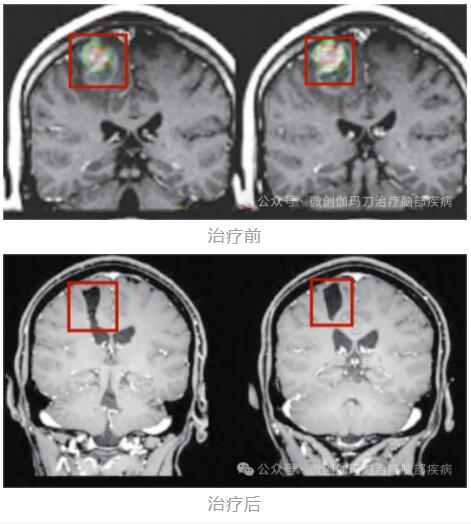

伽玛刀治疗黑色素瘤脑转移